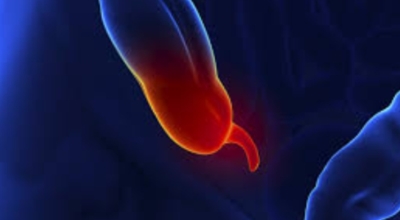

맹장염은 맹장 끝 충수돌기에 나타나는 염증이라고 볼 수 있고, 보통 맹장염으로 알려져 있기는 하나 실질적으로는 부위가 충수돌기이라서 의학 용어로는 충수염이라 하는 단어가 훨씬 정확하다고 합니다. 맹장염(충수염)은 한국 사람들이 수술을 진행하는 질병 5위라고 불릴 만큼 자주 발생하며 해마다 약 10만 명 정도가 수술을 받을 만큼 흔히 나타나는 질환입니다. 복통과 소화불량으로부터 시작하는 맹장염 초기 증상이 발생하는데 많은 분들이 소화기 계통 질환으로 오인해 약만 먹고 그냥 지나치는 경우가 많다고 합니다.

대장이 시작되는 부위를 맹장이라고 하며 그 끝부분에 약 5~10cm 정도의 길이로 꼬리처럼 달린 구조물을 충수 및 충수돌기라고 하는데, 흔하게 말하는 맹장염은 이 충수가 막히거나 눌려서 염증이 발생해 통증이 생기게 되는데 심할 경우 터지는 경우가 발생하기도 합니다.